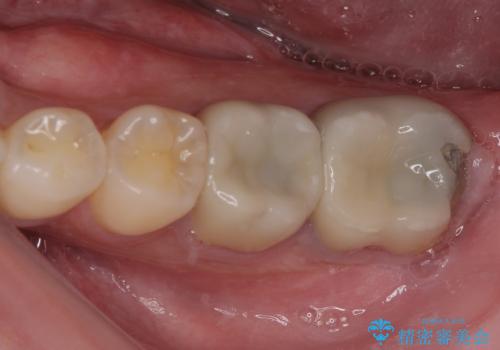

奥歯がズキズキと痛む 奥歯の虫歯治療